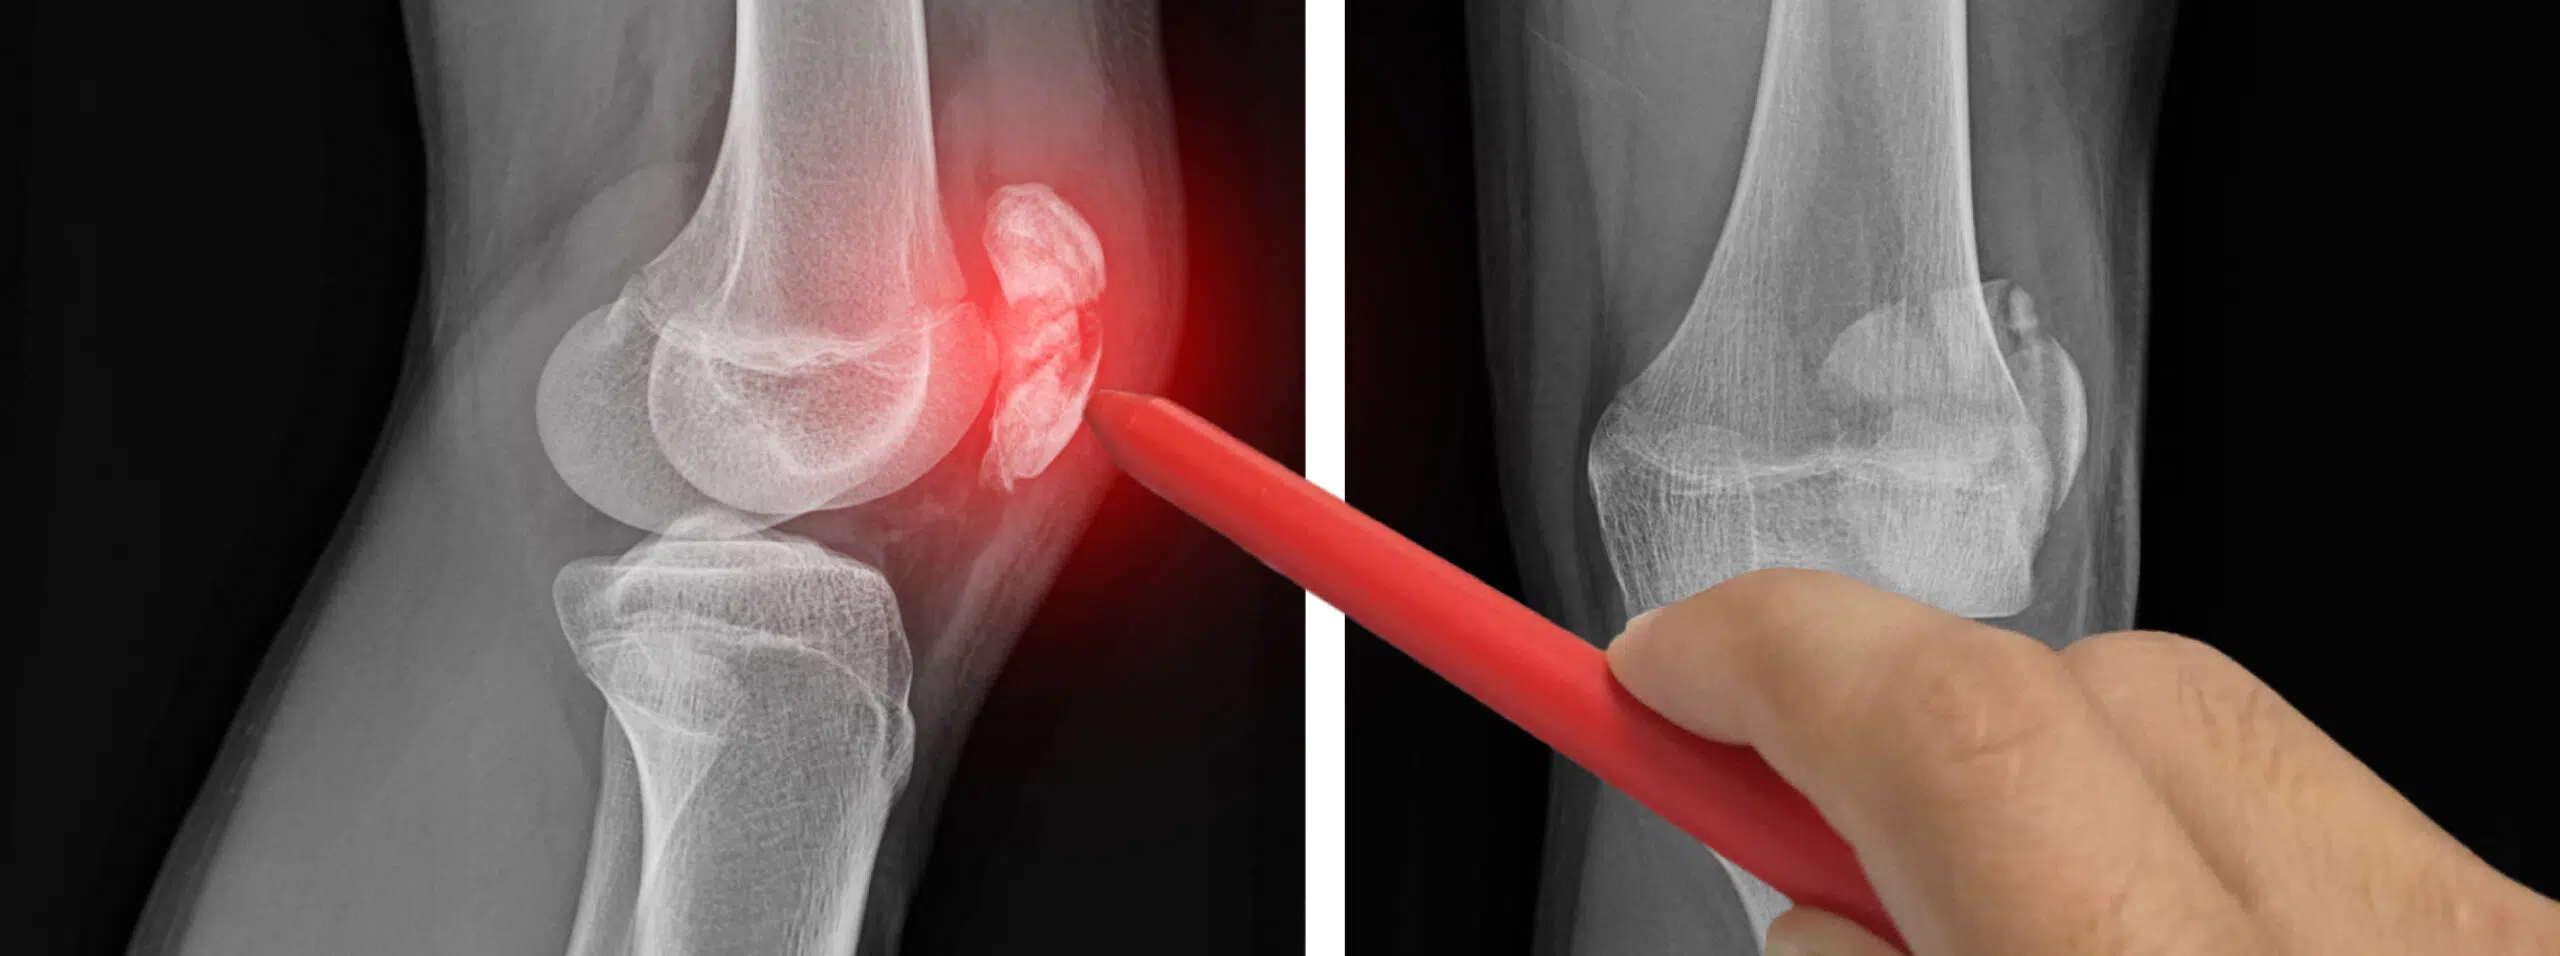

Traditionnellement, certaines infiltrations étaient réalisées « à l’aveugle », en se basant sur les repères anatomiques. Aujourd’hui, les avancées en imagerie permettent d’effectuer ce geste avec une grande précision, grâce à un guidage échographique, radiographique ou scanner.

L’objectif du guidage est d’ assurer que le produit soit injecté exactement au bon endroit, là où l’inflammation est présente.

Le guidage échographique

C’est la méthode la plus courante. L’échographie permet de visualiser en temps réel l’aiguille et la zone à traiter. Elle est indolore, rapide et sans rayonnement.

Idéale pour les infiltrations du genou, de l’épaule, du coude, du poignet ou des tendons.